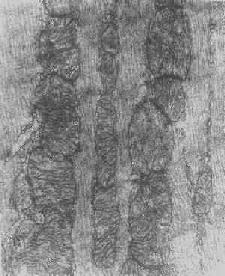

图1-11 线粒体肿胀(基质型)空泡变(心肌缺氧) 3.结构的改变 线粒体嵴是能量代谢的明显指征,但嵴的增多未必均伴有呼吸链酶的增加。嵴的膜和酶平行增多反映细胞的功能负荷加重,为一种适应状态的表现;反之,如嵴的膜和酶的增多不相平行,则是胞浆适应功能障碍的表现,此时细胞功能并不升高。 在急性细胞损伤时(大多为中毒或缺氧),线粒体的嵴被破坏;慢性亚致死性细胞损伤或营养缺乏时,线粒体的蛋白合成受障,以致线粒体几乎不再能形成新的嵴。 根据细胞损伤的种类和性质,可在线粒体基质或嵴内形成病理性包含物。这些包含物有的呈晶形或副晶形(可能由蛋白构成),如在线粒体性肌病或进行性肌营养不良时所见(图1-12);有的呈无定形的电子致

图1-12 线粒体内晶形包含体(进行性肌营养不良症) 密物,常见于细胞趋于坏死时,乃线粒体成分崩解的产物(脂质和蛋白质),被视为线粒体不可复性损伤的表现。线粒体损伤的另一种常见改变为髓鞘样层状结构的形成,这是线粒体膜损伤的结果。 衰亡或受损的线粒体,最终由细胞的自噬过程加以处理并最后被溶酶体酶所降解消化。